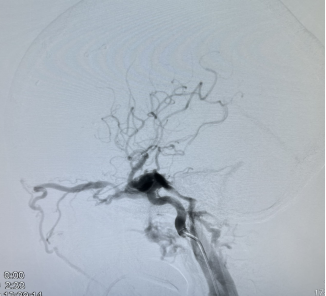

神经外科血管病团队立即为患者进行脑血管造影,分别对颈内动脉、颈外动脉、椎动脉进行造影,同时进行压颈试验,评估血管代偿情况,得出结论:左侧颈内动脉海绵瘘,瘘口流量大,3D旋转不能显示瘘口,向两侧颈内静脉引流,左侧眼静脉粗大,左侧岩下窦显影,前交通动脉代偿良好,后交通动脉代偿差。

全科讨论手术方案后,一致认为要栓塞瘘口并保护好左侧颈内动脉的通畅,遂决定采用静脉途径使用“钢筋混泥土”(同时使用弹簧圈和液体栓塞剂)结构牢牢堵住瘘口。

3月16日13点,张卫东带领团队为患者行颈内动脉海绵窦瘘栓塞术,同时行股动脉、股静脉穿刺,微导管翻山越岭后进入海绵窦。为确保左侧颈动脉不受干扰,于颈动脉内置入球囊予以保护。

(栓塞术前,瘘口流量大,深部静脉危险引流)